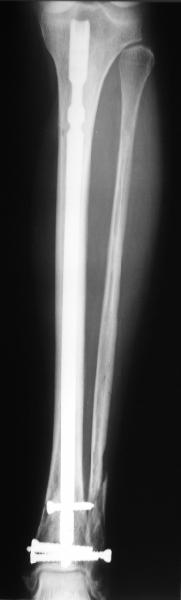

A typical case is attached, also an image with intra-op reduction obtained by a small wire distractor, in the moment of insertion a Poller wire in AP direction. Fixation by a SIGN nail. Despite the fibula was not fixed healing was obtained with the unchanged alignment.

Very interesting application, but is the final position in a little distal varus with some fibula

distraction? Would that have been eliminated by fibula plating?

At least both the ankle mortise and tibial alignment look acceptable, don't they?

I am just trying to illustrate that prevention of 1)tibial valgus and 2)loss of reduction can be provided without fibular plating. Small changes of conventional nailing techniques allow to maintain reduction of the tibia reliably without adjunctive fibular stabilization.

In delayed cases acute length restoration performed only in the tibia may leave the fibula shortened thus change the mortise. So it is reasonable to restore length of both bones simultaneously by distractor and fix the fibula not with open reduction and plating but just by a single perQ screw. Example attached.